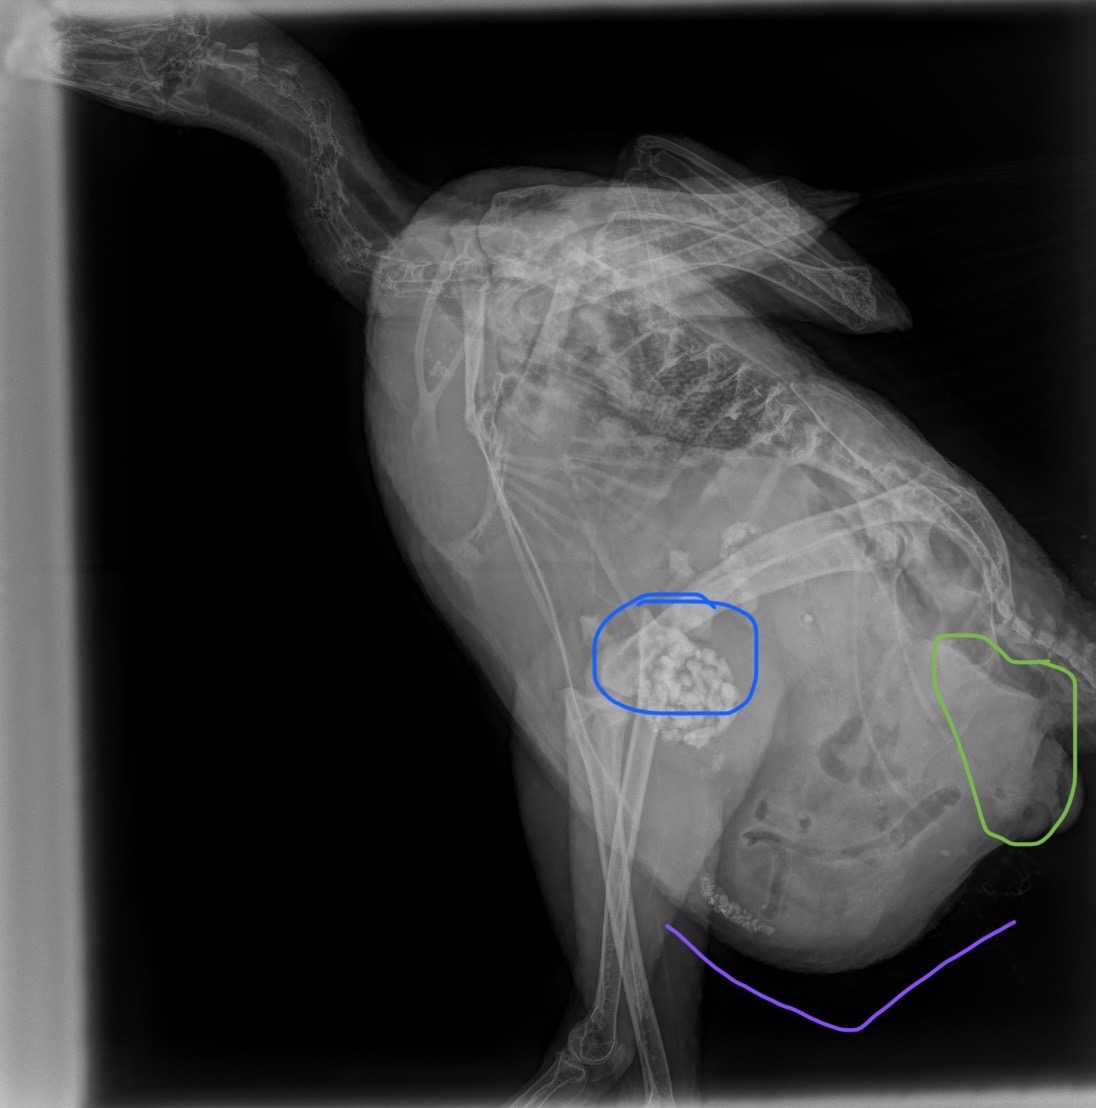

I have a Liege Fighter hen who is 11 months old and may have Leukosis. Her intestines, gizzard and other organs are lower and further down in her body, causing her crop and respiratory system to be unusual. Her crop and stomach get huge when she eats and it causes slight respiratory distress, but she doesn’t seem fazed by it. She’s super active and eats/drinks/grazes normally.

There is also the slightest possibility it could be a bornavirus issue based on symptoms and research my vet did. Her bursa seem to be enlarged/inflamed and not sure if that is tied to Leukosis or something else. – Cheri Lyon

Dr Bowes: Leukosis is the disease (i.e. tumour) state of Lymphosarcoma. Avian bornavirus causes proventricular dilation disease, a progressive neurological and gastrointestinal disease, which is not recognized in chickens. I agree that her gizzard should be lower and wonder why her abdominal area is pushing it up. Of concern, is the size of her bursa (you shouldn’t be able to see it in an 11 month old hen). Unfortunately the X-rays are too difficult to read to give you more information.